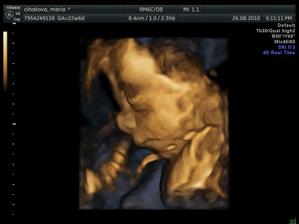

Pat a Mat 24 t.t. 4D

...noo trvalo to dlho, chlapci sa nechceli ani fotiť ani natáčať...takže máme jedna vydarenú foto a potom iba zadočky a pod.....🙂))

ničmenej, bolo to zlaté vydieť ako sa smejú a otvárajú pusinky 🙂)